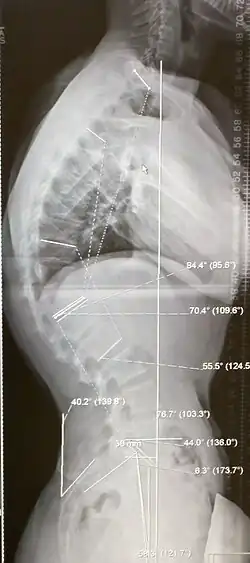

Scheuermann's disease is a skeletal disorder.[3] It describes a condition where the vertebrae grow unevenly with respect to the sagittal plane; that is, the posterior angle is often greater than the anterior. This uneven growth results in the signature "wedging" shape of the vertebrae, causing kyphosis. It is named after Danish surgeon Holger Scheuermann.[4][5][6]

Diagnosis is typically by medical imaging. The degree of kyphosis can be measured by Cobb's angle and sagittal balance.